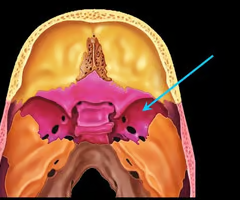

Sella turcica (holds pituitary gland - “Turk’s saddle”)

Cribriform plate of the ethmoid bone (notice olfactory formina in it - for olfactory nerves. Crista galli “rooster’s comb” dura mater attaches here)

Lesser wing of the sphenoid bone

Optic canals (optic nerve)

Optic canals (optic nerve)